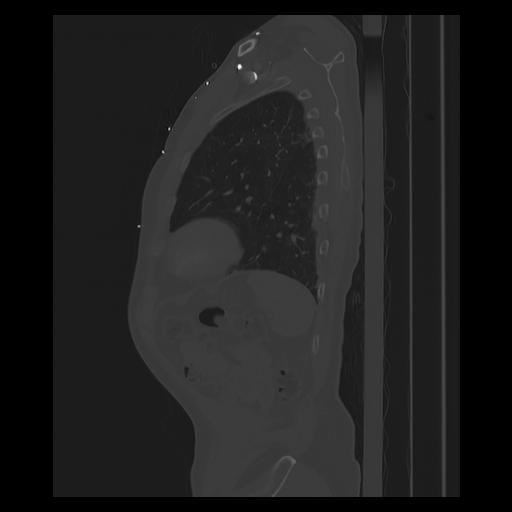

33 PULMON,CE,Sagittal,3.000,PULMON,Sagittal,